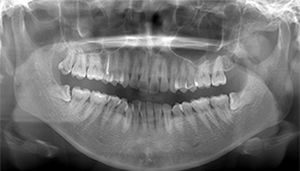

左下親知らずがたまに痛み、

できれば痛くなく抜きたい症例

- 抜歯前写真(レントゲン)

- 抜歯前写真(CT画像)

| 年齢 | 20代・女性 |

|---|---|

| 主訴 | 左下親知らずがたまに痛み、できれば痛くなく抜きたい |

| 親知らずの生え方 | 完全に埋まっている、横向きに生えている |

| 抜歯時間 | 50分 |

| 費用 | 約8,000円(保険診療、CT代含む) |

| 抜歯内容 | 左下親知らずが横向きになって半分埋まっている状態だったため、麻酔を行い、親知らずの奥の歯ぐきに切開をいれ、歯が囲んでいる骨を削り、歯の頭の部分を削って出し、その後根の部分に器具をかけて抜歯しました。 親知らずが一部神経に近い部分があったため、術後に麻痺が出る可能性がありました。このケースでは事前にCTを撮影し、歯の位置、根の方向、神経との距離を確認していたため、幸い麻痺が出ることはありませんでした。 術後1週間経過して糸取りをして治療は終了となりました。抜歯後3日間は腫れと痛みで大変だったが、糸取りをする頃には痛みも腫れも無くなったと患者さまも喜んでおられました。 |